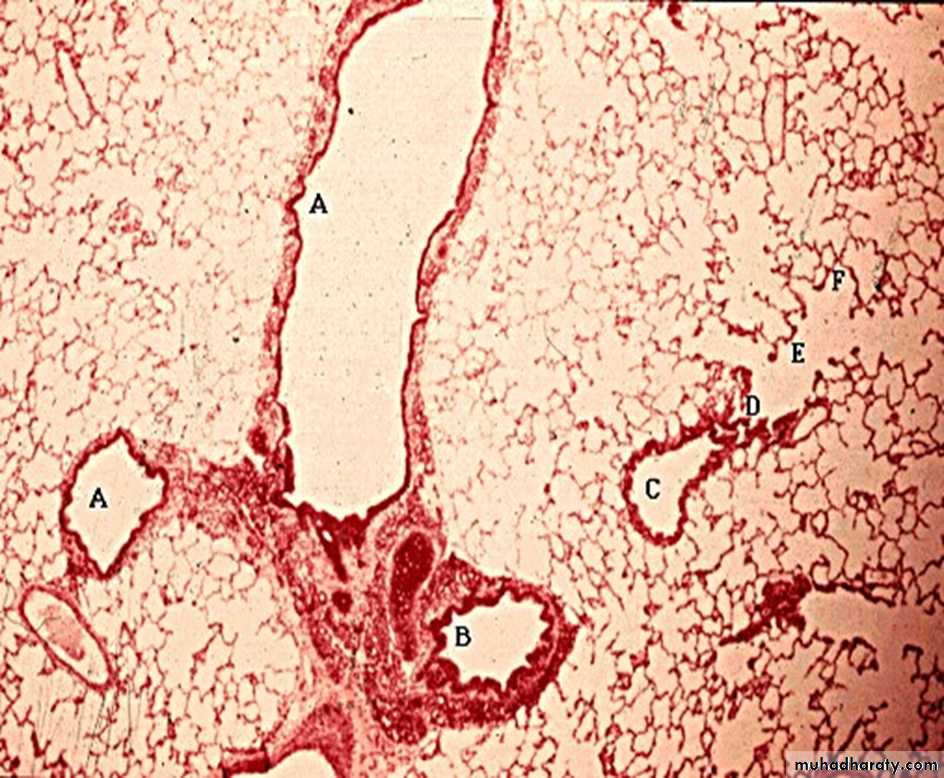

The question about this slide : Name the indicated structures and you may as well name the organ tooA bronchioles ( note the absence of cartilage in their wall)

B is a bronchus ( with a plate of cartilage in their upper left hand corner of its wall )C is a terminal bronchiole branching into D the respiratory bronchial (which can be distinguish by the alveoli interrupting its wall)

E are alveolar duct